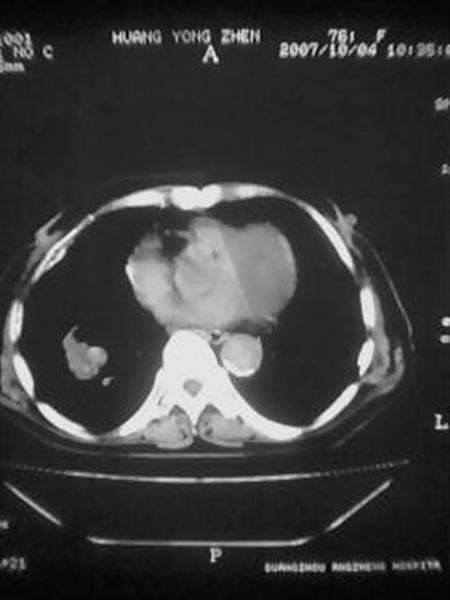

标题: CT10080:F76Y,各位老师发表高见!!! [打印本页]

标题: CT10080:F76Y,各位老师发表高见!!!

右下肺周围型肺癌伴双肺右侧叶间 胸膜及右肺门淋巴结转移

考虑:肺癌伴肺、胸膜 纵隔淋巴结转移可能性大!